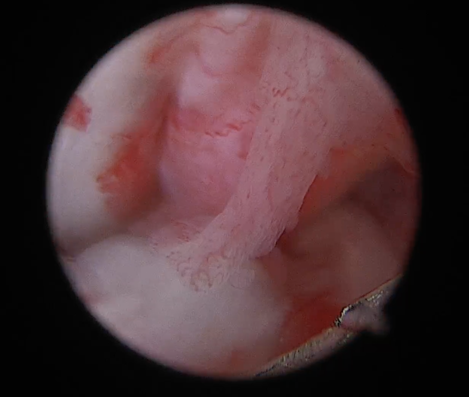

2) 관절경 확인

- 완전히 끊어진 게 아니라 일부만 찢어진 경우에는 drawer test나 tibial compression test가 각도에 따라 약하게 나오거나, 어떤 때는 명확하지 않을 수 있습니다

관절경은 관절 안을 직접 보니까, “진짜로 어느 부위가 얼마나 남아 있는지/어느 밴드가 손상인지”를 눈으로 확인할 수 있어 진단을 더 확실하게 만들어 줍니다.

- CCLD에서 meniscus가 같이 찢어지는 경우가 흔하고, 이게 있으면 통증·파행이 더 심해지거나, 수술 후에도 절뚝거림이 남는 원인이 될 수 있습니다.

특히 meniscus는 관절 밖에서 촉진이나 X-ray로는 “직접” 확인이 어렵고, 클릭 소리가 없거나 증상이 애매하면 놓치기 쉬운데, 관절경으로는 찢어진 부위/불안정한 조각을 직접 확인하고 필요한 처치를 같이 할 수 있습니다.

.png)

전방 십자인대 손상 확인 된 모습